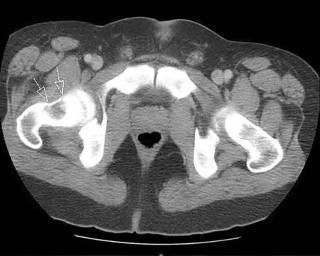

Question 2:

A 32-year-old male is brought to the trauma bay in hemorrhagic shock after a motorcycle crash. An anteroposterior radiograph of the pelvis demonstrates an APC-III injury. A pelvic binder is applied. To maximize reduction of the pelvic volume, at what anatomical landmark should the binder be centered?

Correct Answer: Greater trochanters

Explanation:

Pelvic binders should be centered over the greater trochanters to effectively close the pelvic ring and reduce pelvic volume. Placement over the iliac crests or ASIS can paradoxically widen the true pelvis or fail to achieve adequate reduction in an open-book pelvic injury.